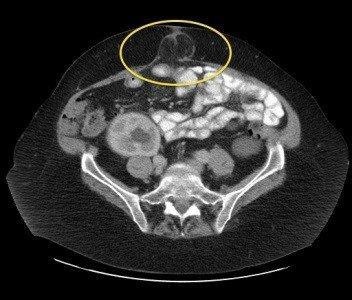

Xarici yırtıqların diaqnozu əksər hallarda klinik olaraq qoyulur, görüntüləmə üsulları erkən mərhələ yırtıqlarda, differensiasiyada, yanaşı xəstəlikləri və yırtığın ağırlaşmalarını müəyyənləşdirmək üçün tətbiq edilir. USM bütün xəstələrdə aparılır, KT isə əməliyyatdansonrakı yırtıqlarda yırtığın ölçülərini və möhtəviyyatını müəyyənləşdirmək və daxili yırtıqları təyin etmək üçün vacibdir. MRT idmançı yırtıqlarını digər xəstəliklərdən (periostit, nevralgiya və s) differensiasiyada ilk seçimdir. Yırtığa böyük şübhə olduqda lakin klinik və görüntüləmə üsulları ilə təsdiq etmək çətinliyi olanlarda laparoskopiya aparıla bilər.

- KT və ya MRT-də qarın divarında defekt, yırtıq kisəsi və yırtıq möhtəviyyatının (bağırsaq, piylik, və digər) görünməsi

- Diaqnozunu əksər hallarda klinik olaraq təyin etmək mümkün olsa da, tərkibini , ölçüsünü dəqiqləşdirmək və differensiasiya üçün KT lazım gəlir.